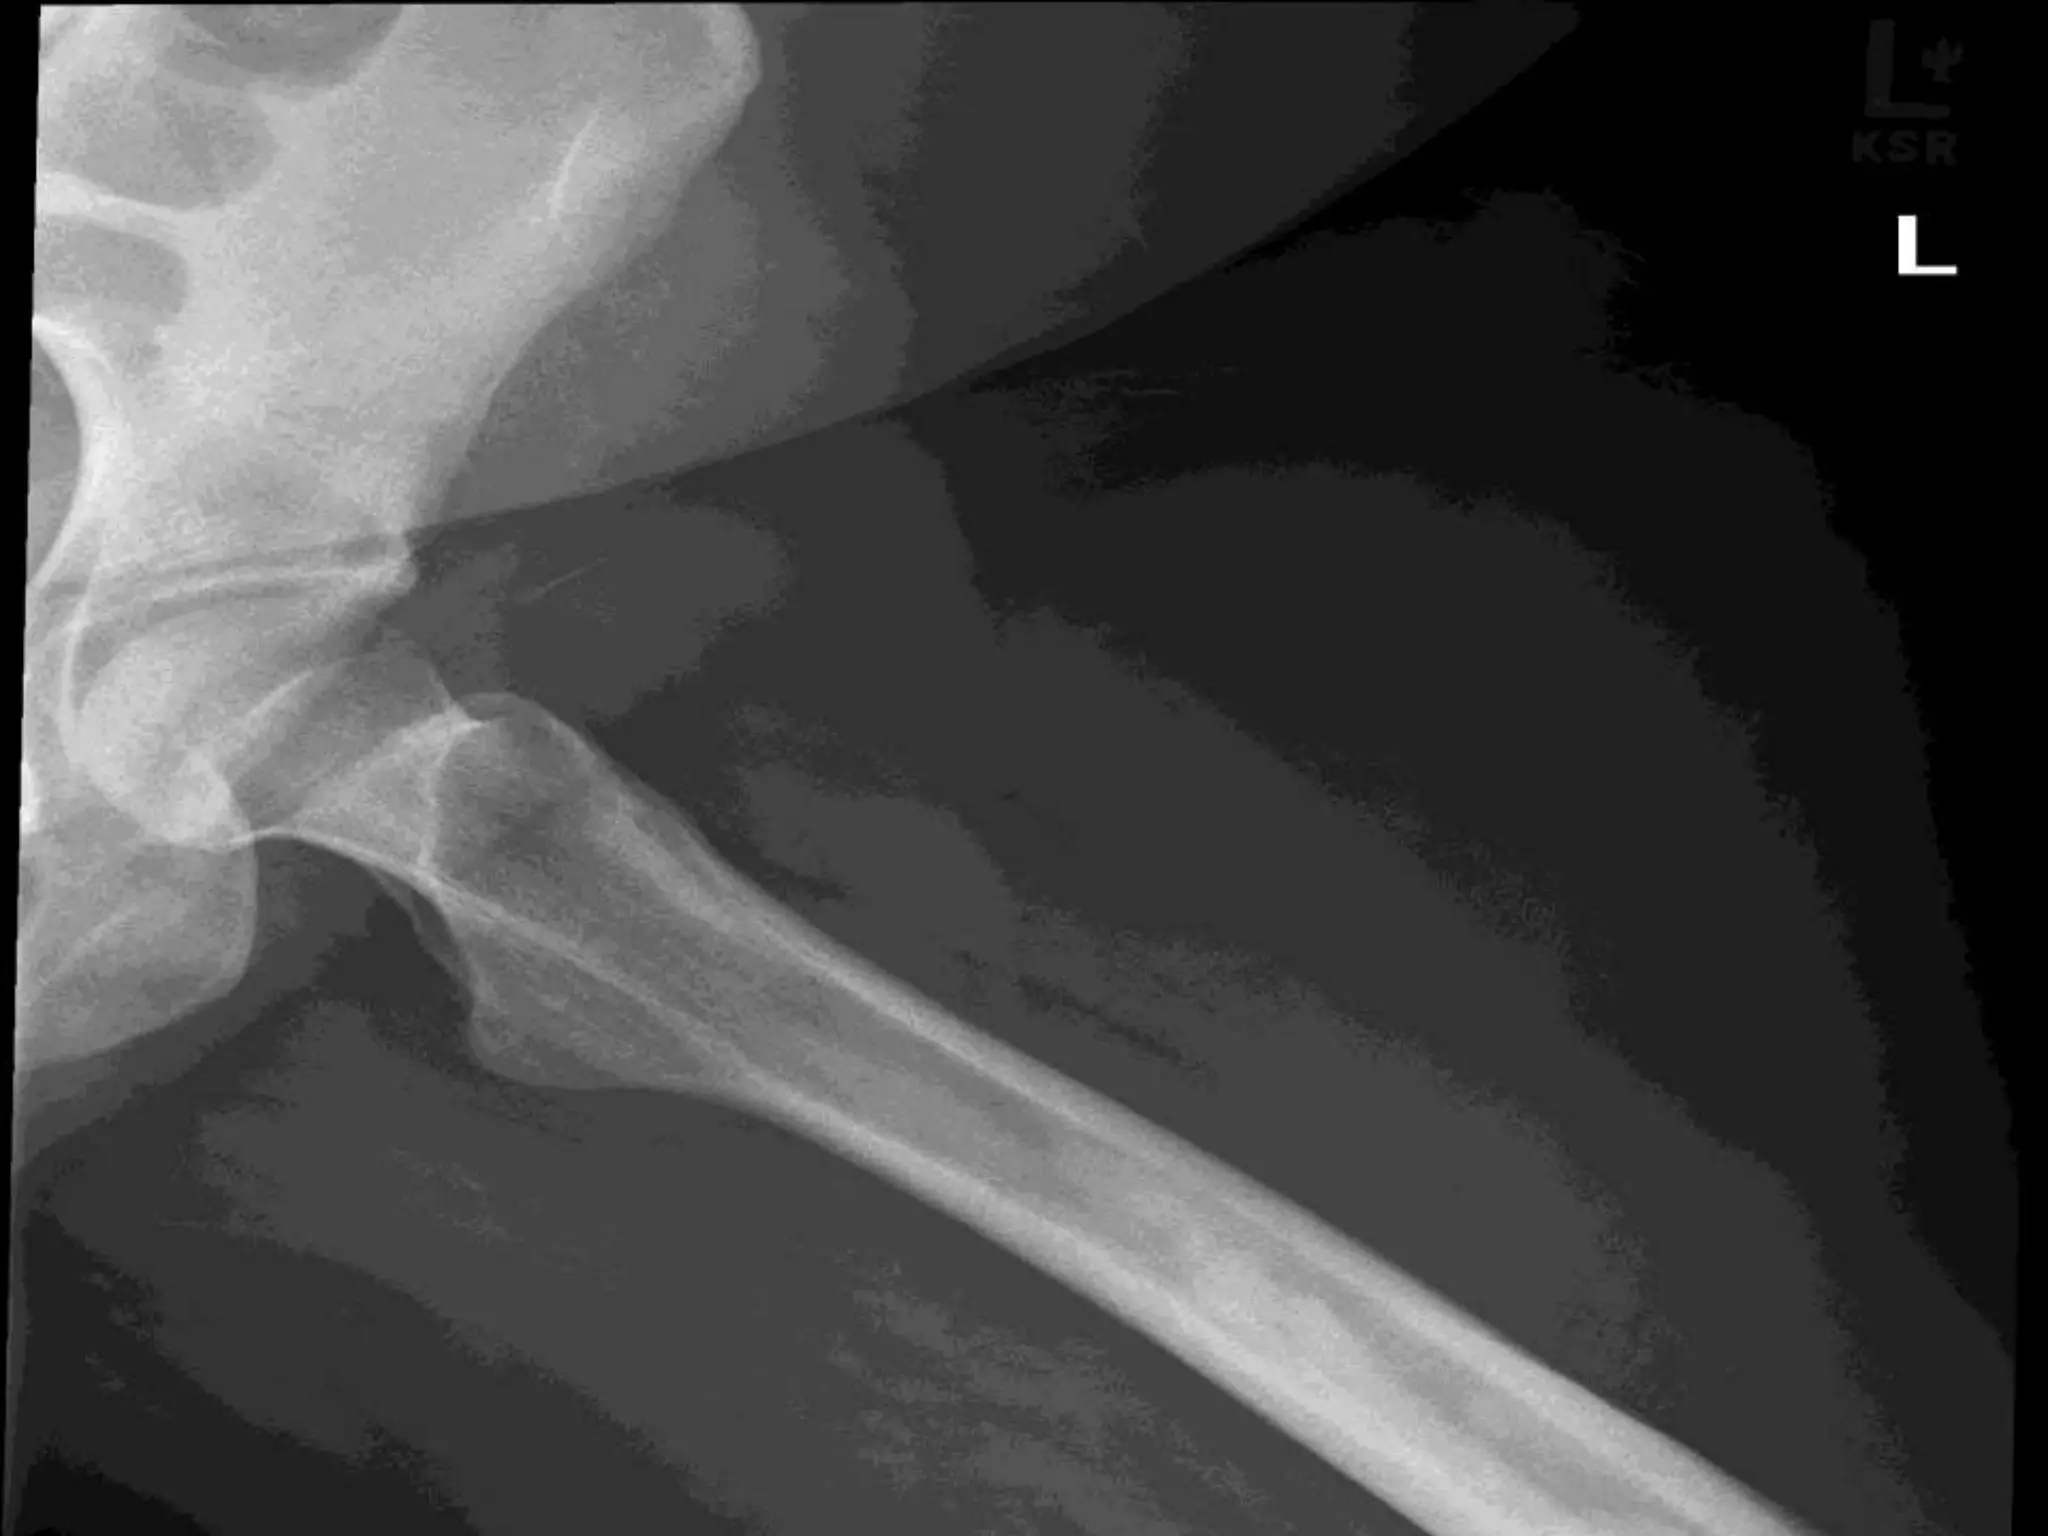

Dyschondroplasia /Enchondromatosis/Ollier’s disease

Rare but easily recognised

Defective transformation of

physeal cartilage into bone

unilateral short limb

Valgus/varus deformity

knee/ankle

Shortened ulna

Bowing radius

Crippled hand

(Fingers/toes have multiple

enchondromata characteristic

of disease)